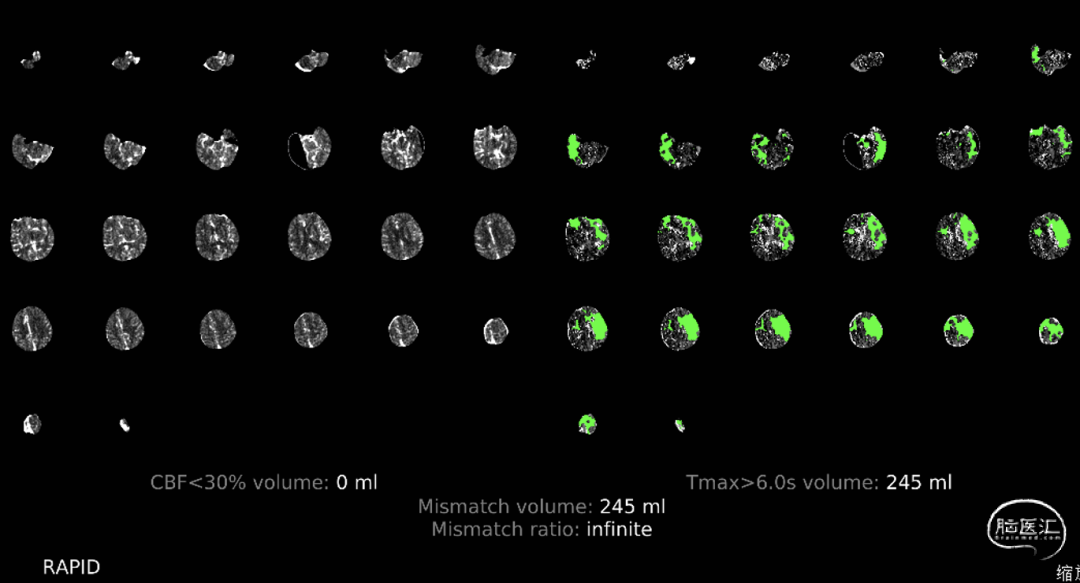

患者醒后卒中,依据指南应在多模式影像学评估下选择最佳治疗方案,急诊绿道完成了一站式RAPID软件AI影像处理。

CTP提示左侧大脑半球大面积低灌注区。

发病超过6h的患者,应利用脑灌注成像技术,明确存在大面积缺血半暗带。患者家属积极并同意治疗。

1.患者高龄,但发病前生活质量较好。本次为醒后卒中左侧大脑中动脉急性闭塞,临床症状较重,基于多模CT及RAPID评估,仍有较大缺血半暗带可以挽救,征得患者家属知情同意后,急诊行脑血管造影+左侧大脑中动脉取栓术,获得了较为满意的预后。